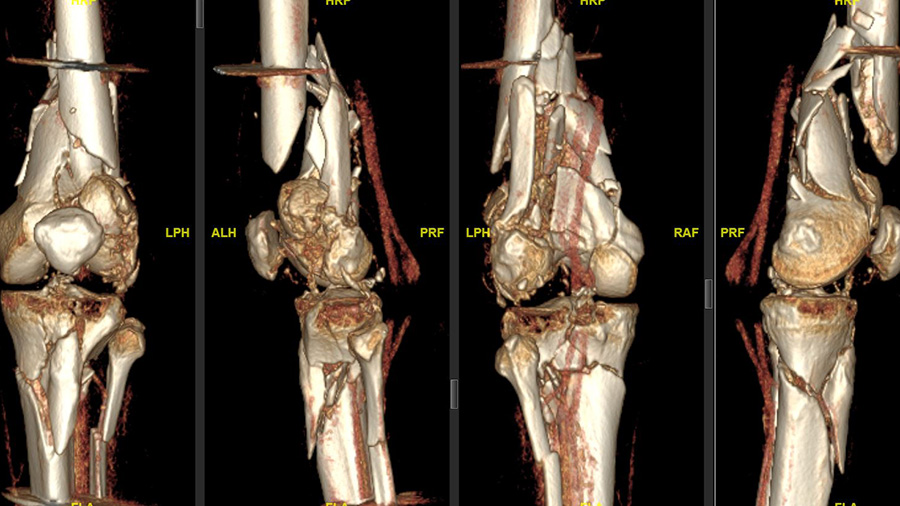

“The patient was driving a car while on holidays in Mexico and was hit from the left side. He had serial rib fractures, a nasty, open fracture of his left elbow, and an open, complex floating knee injury, a comminuted distal femoral fracture, and a proximal tibial fracture on the left side as well as a proximal tibial fracture on the other side,” Sommer explains, noting that after about two weeks of care in Mexico, the patient was flown back to Switzerland by Rega Swiss Air-Rescue. “He arrived at our hospital with an external fixator on his left knee and elbow, and was in generally good shape. First, my colleague fixed his elbow and right tibia; and, unfortunately, the patient had also an injury to his left radial nerve that had to be reconstructed.”

“The knee needed better reduction and stronger fixation than just this joint-bridging external fixator, which was quite clear. I think the biggest risk without this surgery would have been intra- and extraarticular nonunion of the femur because it was a multi-fragmented and open fracture,” Sommer says. “The goal, of course, was to stabilize both legs and bring all fractures back to healing and functioning as well as they were before the accident: intraarticular congruency with well-aligned bones (correct length, rotation, and axis), and a moveable, stable, and hopefully pain-free joint.”